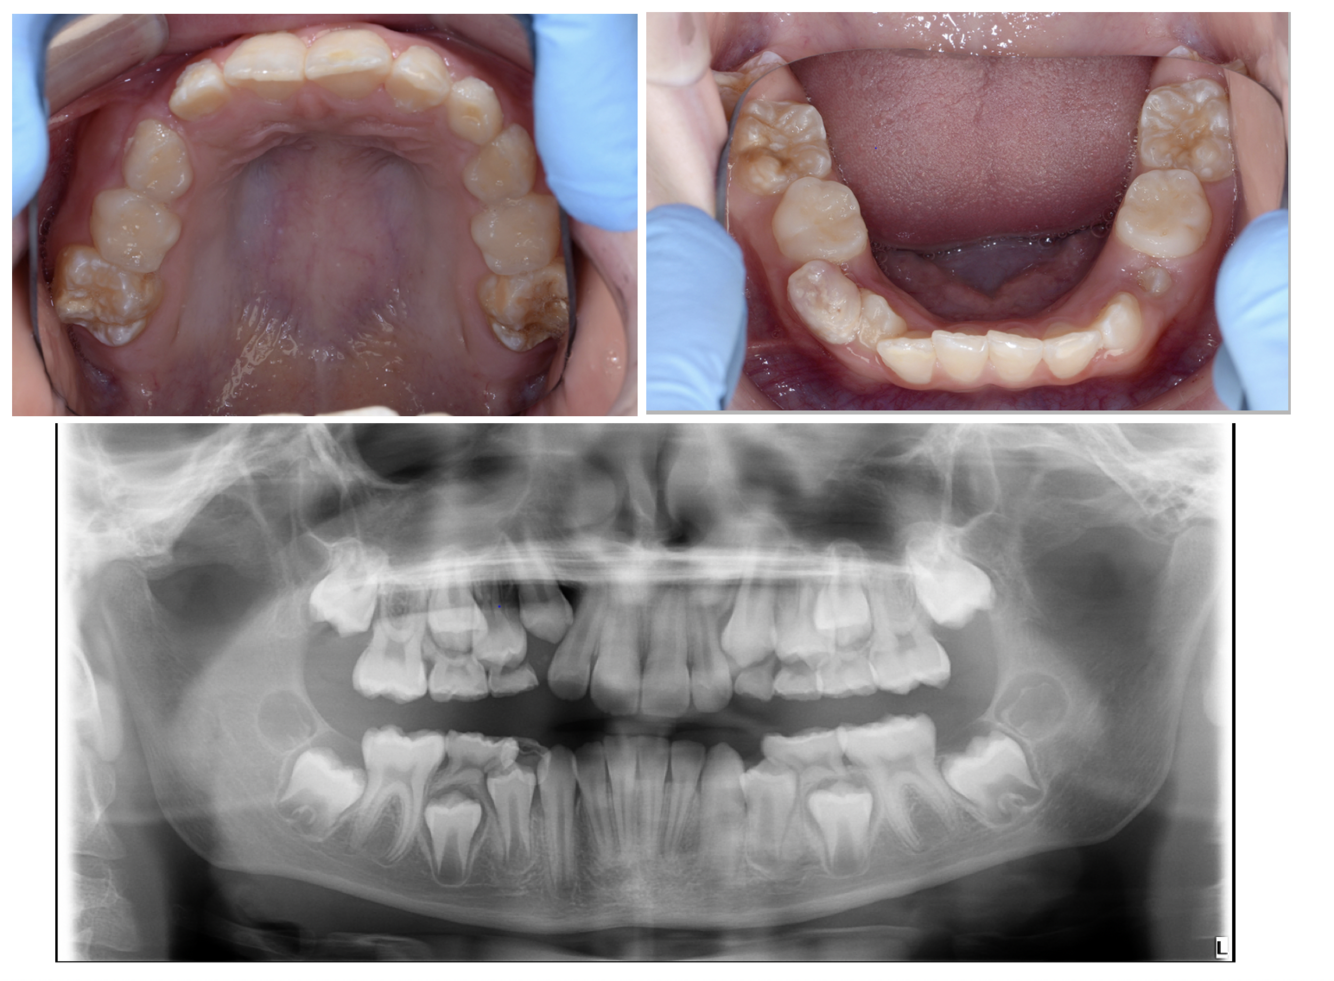

Q

• 10 year old patient

• MIH in upper and lower molars permanent molars

• Anterior tooth wear (NCTSL)

• Upper moderate crowding

• Lower mild crowding

What are the favourable signs of extraction of permanent first molars? (4)

A

• Patient age is 8-10

• Calcification of the bifurcation of the 7s

• Calcification of the 8s

• Class I incisor relationship